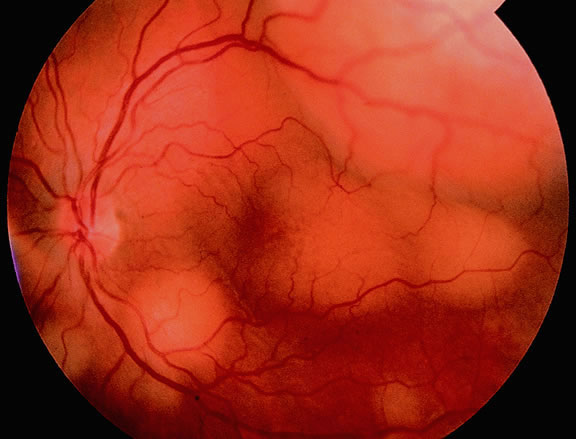

Ultrasonography can support the diagnosis of ciliary body or choroidal melanoma and is a particularly helpful way of disclosing tumors in eyes with opaque media.54 Ultrasonographic studies can alsodemonstrate areas of extrascleral extension. A scan ultrasonography shows a high internal spike and low internal reflectivity. B scan ultrasonography shows characteristic acoustic hollowness and choroidal excavation (Fig. 23). Hemangiomas and metastases usually appear acoustically solid because they contain multiple acoustic interfaces.

Fig. 23. B-scan ultrasound, choroidal melanoma.

The diagnosis of intraocular metastasis usually is made by slit lamp biomicroscopy and ophthalmoscopy in the patient who has been carefully questioned about a past medical history of cancer. Ancillary techniques such as intravenous fluorescein angiography and ultrasonography often can assist in making the diagnosis. Metastases generally begin to show hyperfluorescence in the late venous phase fluorescein angiography, somewhat later than most melanomas or hemangiomas.48,54 Metastases have many acoustical interfaces because they are composed of nests, cords, and island of tumor cells surrounded by stroma. Hence, they show high internal reflectivity on A scan ultrasonography and appear acoustically solid in B scan, characteristics they share with hemangiomas (Fig. 49). In cases in which the results from other studies are equivocal, cytopathologic examination of material obtained by fine-needle aspiration biopsy may establish the diagnosis.82,83

Fig. 49. B-scan ultrasound, choroidal metastasis. Placoid tumor has high internal reflectivity.